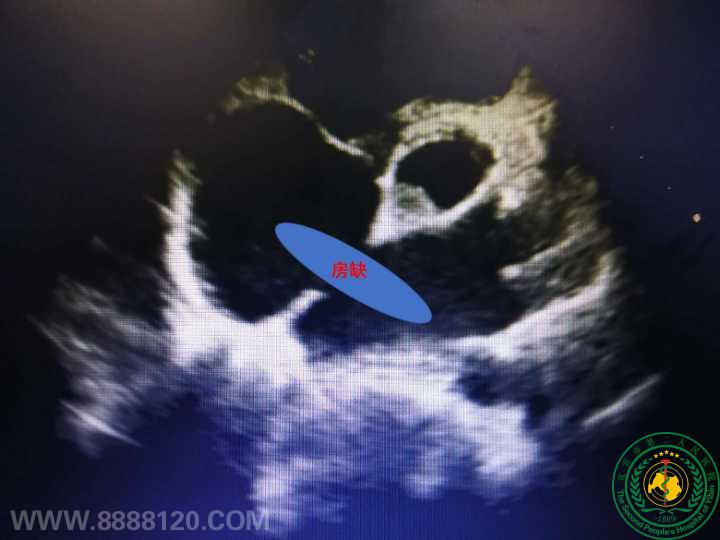

宜宾首例超声引导经胸房缺封堵术在我院成功开展

2018年9月27日,我院胸心外科联合麻醉科、超声科、手术室等,多科室协作成功为一名先天性心脏病(房间隔缺损)的病员实施超声引导下房缺封堵术,手术切口约3cm,手术过程非常顺利,历时1小时左右,术毕彩超提示房缺血液分流完全消失,术后第二天下床活动,术后第三天康复出院回家疗养。

近年来,先天性心脏病房间隔缺损的微创治疗技术发展非常迅速,超声引导下经胸房缺封堵术已经成为一种广泛应用的微创技术,手术通过胸骨下端旁微小切口,在超声引导下穿刺植入房间隔缺损封堵伞封堵缺损,使患者血流动力学恢复正常。该例手术的成功开展,标志着宜宾市二医院先天性心脏病微创外科手术领域在成功开展胸腔镜下房间隔缺损修补手术基础上又有了新的突破。